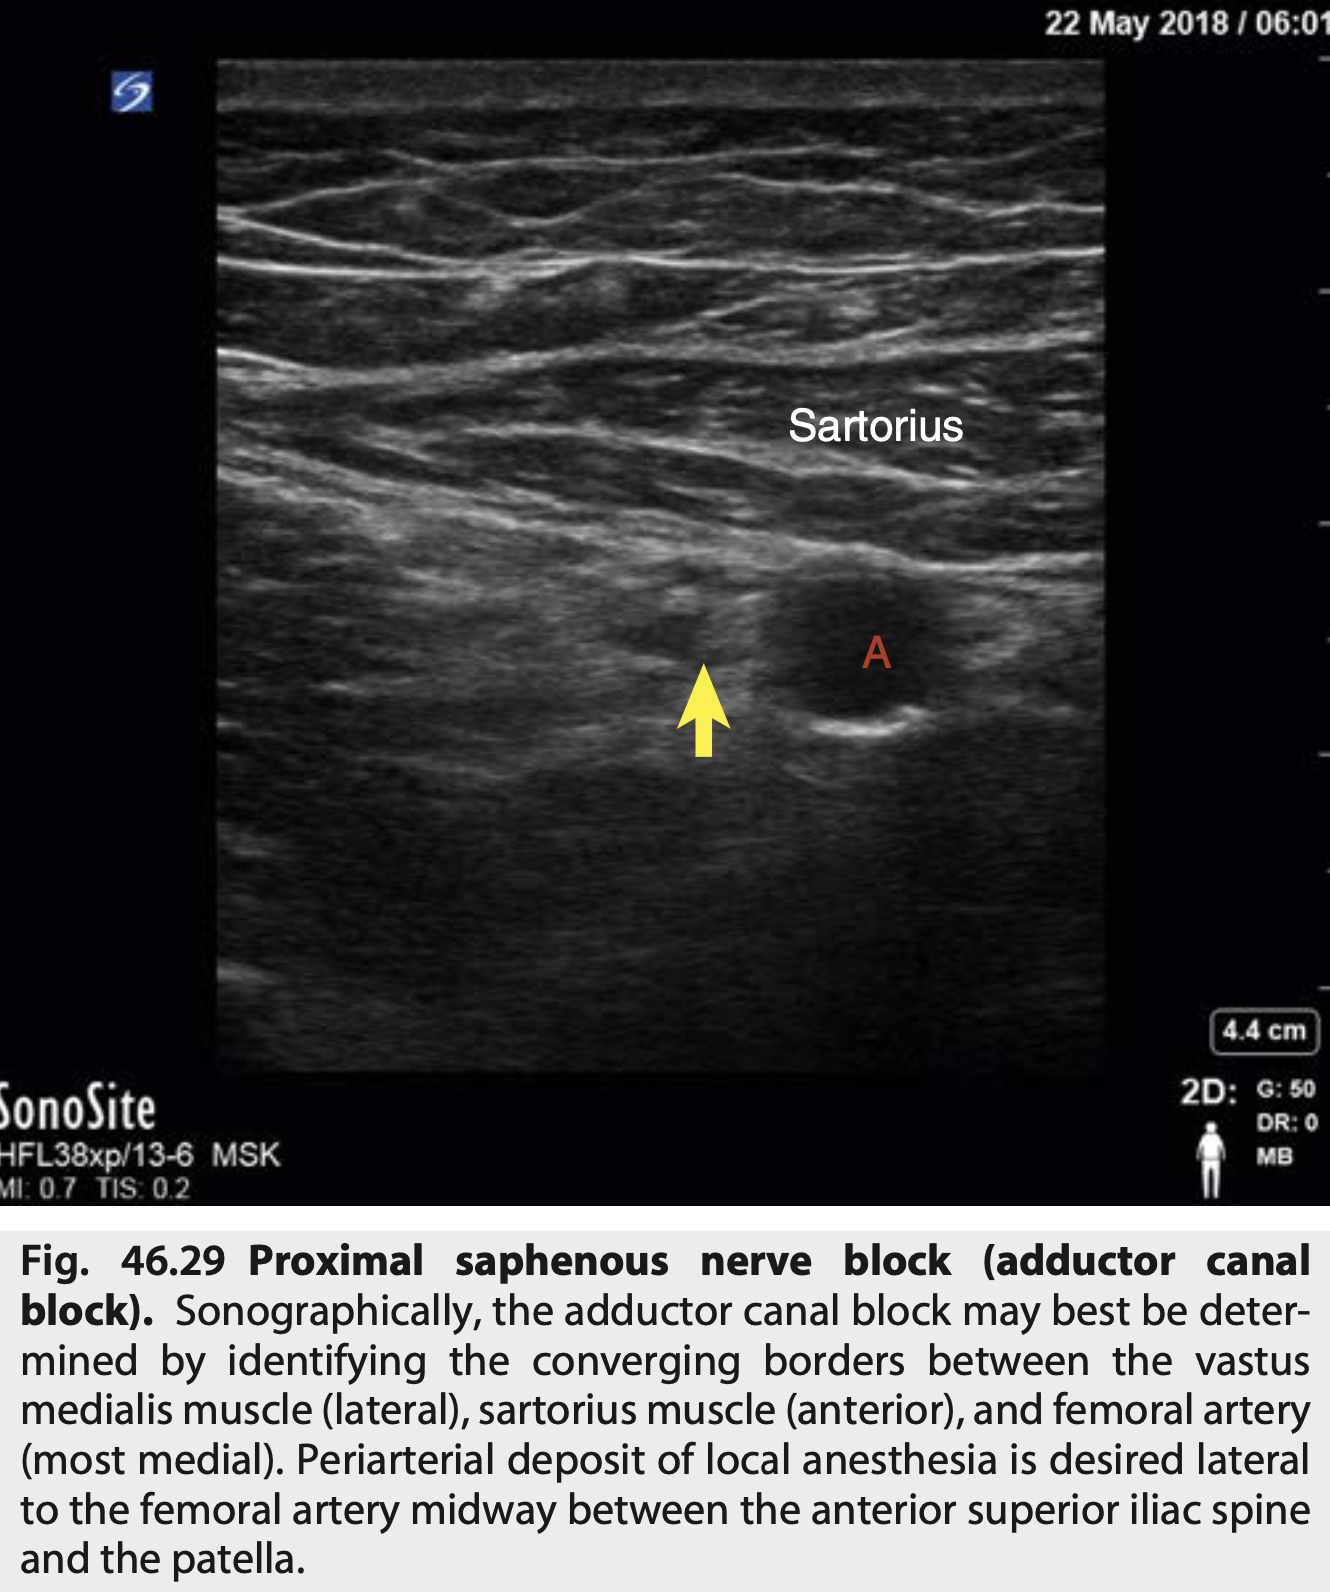

Onde deve ser colocado o AL no bloqueio de n. Safeno?

Periarterial deposit of local anesthesia is desired lateral to the femoral artery midway between the anterior superior iliac spine and the patella.

Identificar as estruturas conforme a imagem do bloqueio femoral

* Agulha vem lateralmente e sente a resistencia das duas fascias ("duplo-click") * 10-15ml AL

Qual o bloqueio conforme a figura?

Nervo Safeno * Ramo terminal exclusivamente sensitivo

Identificar as estruturas conforme a imagem do bloqueio Safeno

* vasto medial e lateral é bem parecido * O nervo esta antero-lateral * Atencao que o Vasto MEDIAL esta Antero-LATERAL * O Adutor Magno é o mais póstero-medial * 10ml de Anestesico local - se mais, pode subir e pegar fibras motoras do femoral